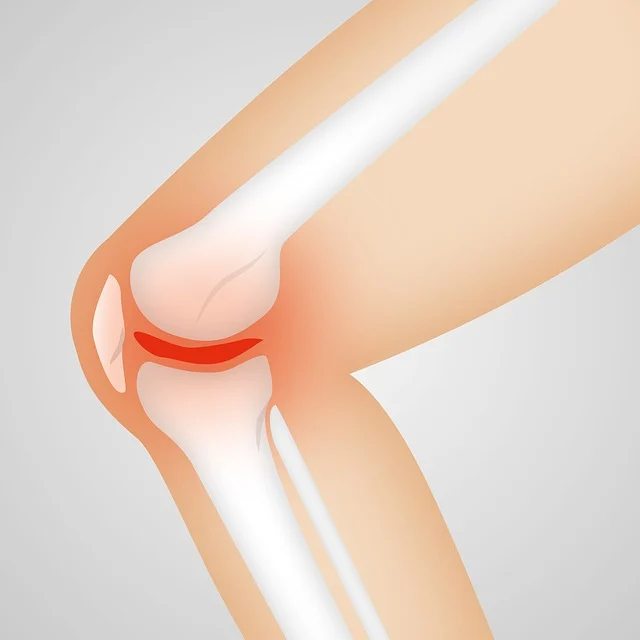

- 글루코사민 & 콘드로이틴

- 연골을 형성하는 성분으로, 관절의 윤활 작용을 돕고 연골 손상을 예방합니다.

- 특히 퇴행성 관절염 예방과 통증 완화에 효과적입니다.